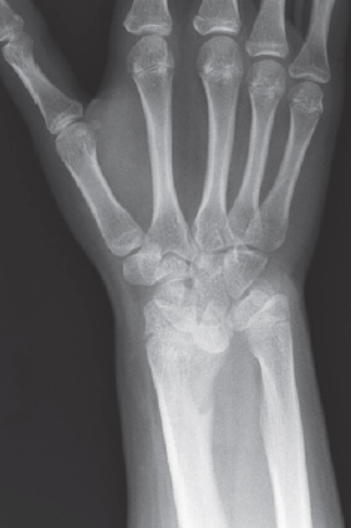

Mulher queixa-se de deformidade em punho e apresenta a seguinte radiografia.

Qual é o diagnóstico?

ADeformidade de Madelung